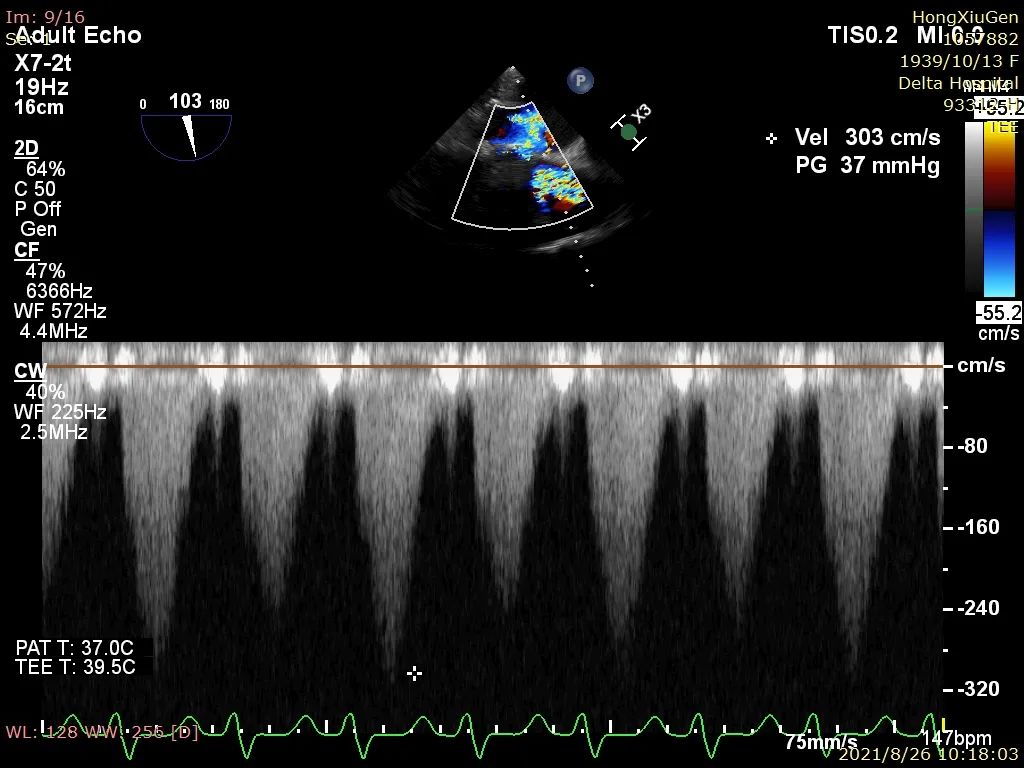

4、180次/分快速起搏下以22mm 球囊进行第一次预扩张,扩张同时造影示明显腰征,球囊受挤压上跳。扩张后超声示跨瓣压差37mmHg,峰值流速303cm/s,主动脉狭窄情况得到改善,主动脉瓣叶活动性增强;

5、180次/分快速起搏下以22mm 球囊进行第二次预扩张,扩张同时造影示明显腰征,球囊受挤压下滑,右冠显影不明显,考虑灌注不良,超声示两次球扩未造成患者主动脉根部明显损伤变形;